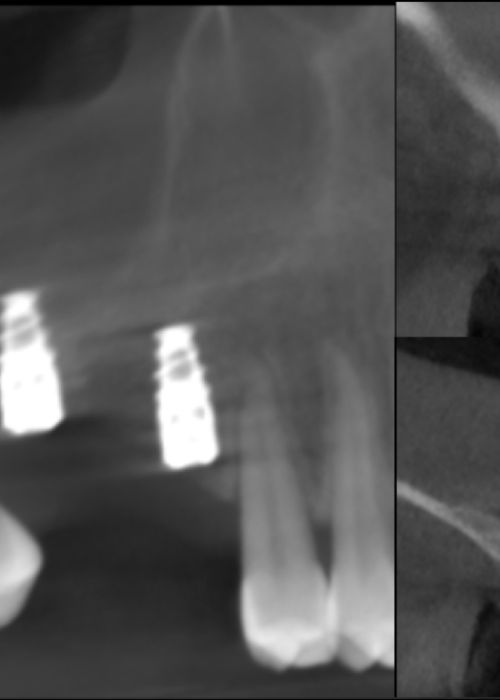

Clinical, radiographic and histomorphometric behaviour of the autologous tooth as a biomaterial in lateral access maxillary sinus elevation. Case report with six months of post-prosthetic loading follow-up

Comportamiento clínico, radiográfico e histomorfométrico del diente autólogo como biomaterial en elevación de seno maxilar de acceso lateral. Caso clínico con seis meses de seguimiento post-carga protésica